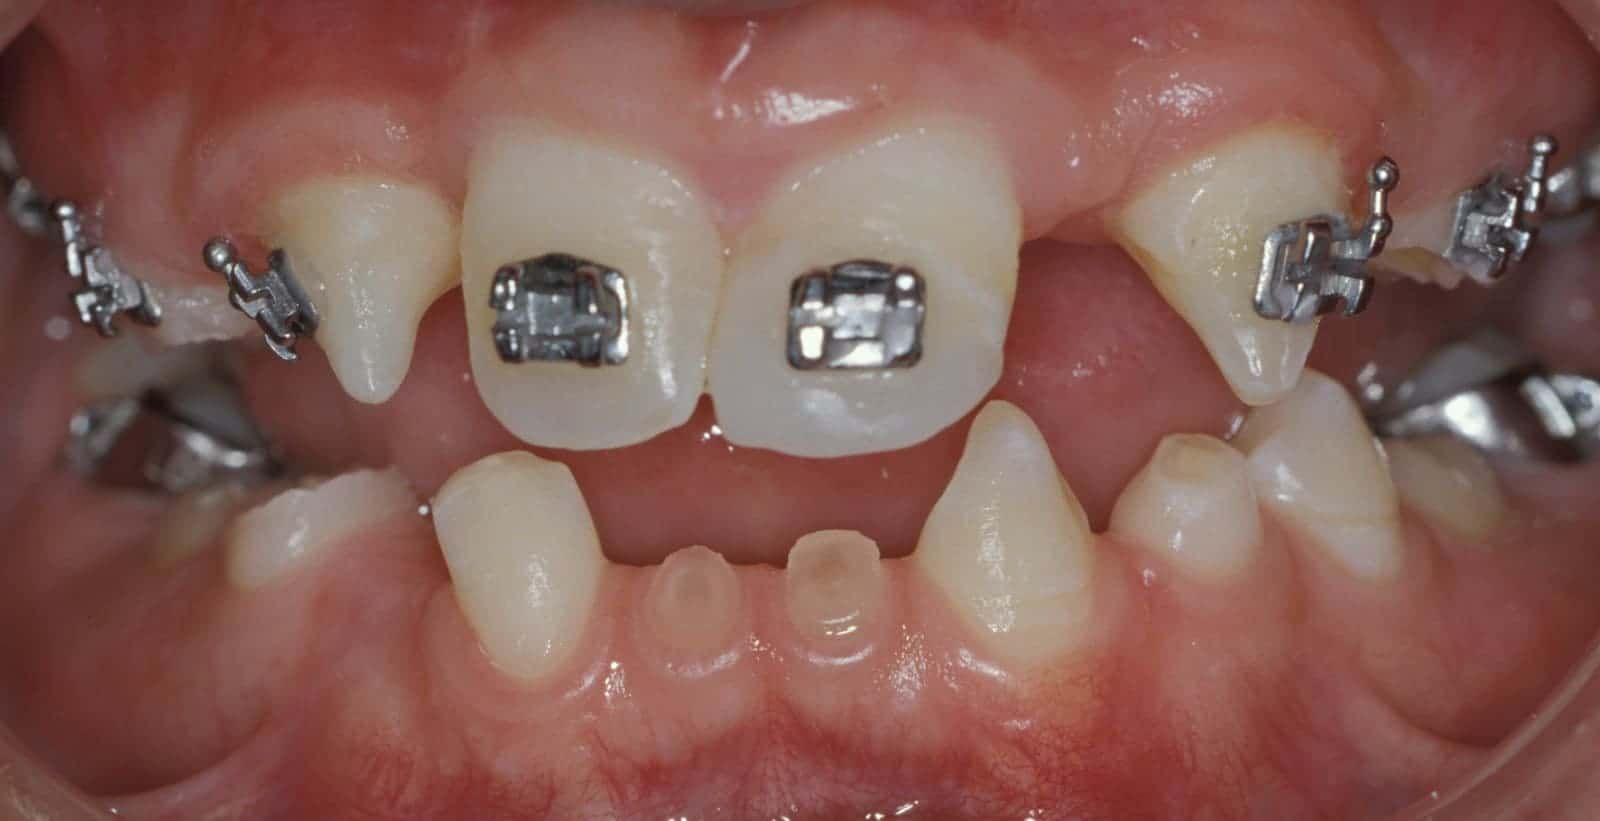

Case Study Details

Congenitally Missing Teeth; Full Mouth Reconstruction/Rehabilitation; Increased Occlusal Vertical Dimension; Pre-Orthodontic Treatment; Ceramic Crowns-bonded; Implant Crowns

Before: Patient is missing 19 adult teeth. Treatment to replace the missing teeth began at age 12 and was completed at age 21. Treatment involved a team approach, with an Orthodontist, Oral and Maxillofacial Surgeon, and Prosthodontist (Dr. Leopardi) heading the team. Orthodontic therapy was performed first to move existing adult teeth to allow for implant tooth replacement therapy in missing teeth sites (tooth-implant-tooth relationship).